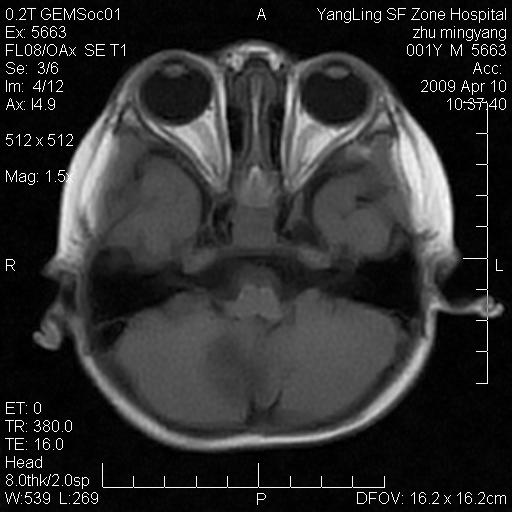

患者:1岁半,两天前外伤收住我院,ct检查小脑占位

考虑星形细胞瘤,建议增强

髓母细胞瘤或血管母细胞瘤,增强后可以鉴别;影像资料见 <。鱼博浪老师的《中枢神经系统ct与mr鉴别诊断》 小脑部肿瘤章节。

髓母细胞瘤或血管母细胞瘤!支持!

支持考虑髓母细胞瘤

考虑----髓母细胞瘤可能性大

考虑髓母细胞瘤或室管膜瘤。

支持髓母细胞瘤。

考虑髓母细胞瘤。

考虑髓母细胞瘤或星形细胞瘤

考虑髓母细胞瘤.

小脑肿瘤.考虑髓母细胞瘤可能.

就病灶部位及临床资料首先考虑髓母.